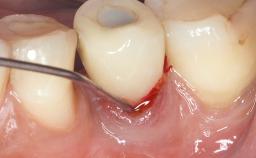

Treatment of Peri-Implant Mucositis at a Zirconia Implant

Frank Schwarz, Ausra Ramanauskaite

Recent clinical studies, most with short-to-medium term observation periods, have reported on the favorable clinical performance of zirconia implants in terms of survival rates, clinical, and radiographic outcomes (Roehling and coworkers 2016; Roehling and coworkers 2017; Rodriguez and coworkers 2018; Lorenz and coworkers 2019). Nonetheless, a rather high incidence of peri-implant disease at zirconia implants (39% of implants) was noted throughout a two-year period, highlighting the need for treatment protocols of peri-implant diseases at zirconia implants (Becker and coworkers 2017).